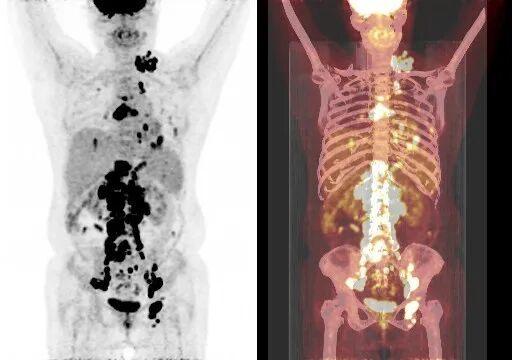

在全球,结直肠癌是发病率位居第三位、病死率位居第二位的肿瘤。肠镜筛查的普及以及手术方式的提升显著降低了结直肠癌的死亡率,但仍有一部分患者在初诊时已发展为晚期,失去手术根治的机会,且预后较差,5年生存率仅12%。许多转移性结直肠癌(mCRC)患者在经历一线治疗后,面临无药可用的困境。近年来,随着靶免联合治疗在系统治疗中逐渐前移,各种靶向治疗药物在mCRC的诊疗中也越发举足轻重。本文分享2例晚期结肠癌患者的诊疗经过,呈现瑞戈非尼在二线治疗为患者带来长生存的治疗价值及其良好的后线应用前景,以期为临床医生提供诊疗借鉴。 病例提供:海军军医大学附属长征医院 王湛 王湛 病例基本情况 一般信息:女 ,58岁。2020年10月,患者无明显诱因出现腹胀,无伴随症状,未予重视。后腹胀进行性加重,2020年11月中旬下腹部隐痛,与进食及体位变化无关,无肩背部放射痛。 辅助检查: 腹部超声:腹腔积液。 腹水脱落细胞病理:腺癌。 腹部增强CT:结肠肝曲癌;腹盆腔积液,腹盆腔腹膜多发转移。 结肠镜(2020-12-4):升结肠近肝曲见隆起型新生物,范围约4cm,新生物表面分叶状,质脆,触之易出血。肠腔狭窄,内镜尚可通过。 2020-12-8病理:横结肠,中分化腺癌,含部分粘液腺癌。 一线治疗2020-12-03至2021-02-24 CAPEOX+贝伐珠单抗 治疗4周期 病情进展,腹胀、腹痛加重,腹水增加。 2021-3-31 PET-CT:腹腔内及腹膜、脾脏、纵隔及右侧心膈角区、左侧锁骨区多发代谢增高灶,结合病史,考虑转移;双肺转移;腹腔及盆腔积液;结肠显示欠清,请结合肠镜检查;双侧胸腔少量积液,左肺下叶部分不张;双肺少许慢性炎症;右肝血管瘤;左肾结石。;子宫术后,痔疮可能;脊柱退变,腰3不稳,腰3/4、4/5、腰5/骶1椎间盘突出。 PFS:3个月 2021-4-6,完善基因检测(腹水标本):KRAS/APC/TERT/TP53/ target=_blank class=infotextkey>P53 突变,TMB 7.98/Mb,MSS 二线治疗,2021-04-02至2021-12 2021-3-31 2021-6-2 2021-8-6肠镜:结肠镜顺利插至回盲部,回盲瓣呈唇状。结直肠粘膜呈桔红色,光滑湿润,有光泽。血管纹理呈树枝状,清晰可见。 PFS:8月 三线治疗,2021-12-13至2022-01-23 三氧化二砷 2021-6-2 2021-11-22 2021-11-22 2022-2-8 PFS:2月 四线治疗,2022-02-10 化疗+免疫+瑞戈非尼+三氧化二砷 2022-2-10开始使用小剂量化疗(雷替曲塞+奥沙利铂+伊立替康)+免疫(信迪利单抗)+瑞戈非尼+三氧化二砷治疗。 疗效评估(2022-9-20):患者病情再次取得缓解。 2022-9-22至今采用维持治疗,降低治疗强度:雷替曲塞 +信迪利单抗+瑞戈非尼+三氧化二砷 2022-9-20 2023-2-8 PFS:13个月+ 该患者为中年女性,诊断为晚期多发转移性结肠癌,基因检测提示KRAS突变,BRAF、NRAS野生型,微卫星稳定,无法进行根治性切除。一线治疗加予CAPEOX联合贝伐珠单抗,治疗4周期后出现病情进展,腹胀、腹痛加重,腹腔积液增加,二线采用瑞戈非尼联合免疫和化疗,患者耐受良好,1周期后腹胀明显缓解,全身状态、PET-CT、肠镜结果较之前明显改善,继续原方案治疗,PFS长达8月。二线治疗进展后完善基因检测,发现TP53 突变,经与患者充分沟通,三线治疗采用三氧化二砷,疗效不佳。四线治疗在三氧化二砷基础上加用瑞戈非尼+免疫+化疗,患者病情再次取得缓解,PFS 超过13个月。近年来,随着精准医学及靶向、免疫治疗的发展,mCRC的管理与治疗策略的制定也变得复杂,合理选择治疗手段、优化全程管理至关重要。本例患者经历了一线化疗联合免疫治疗后疾病出现快速进展,我们个体化地在二线治疗中应用瑞戈非尼联合方案,患者疾病得到控制,PFS 8个月。在四线治疗方案中,再次挑战瑞戈非尼,依然获得较好的疾病控制效果,目前PFS已超过13个月。基于CORRECT和CONCUR研究,瑞戈非尼用于mCRC三线治疗已积累大量临床数据,目前已成为mCRC三线标准治疗方案。此外,REGONIVO、REGOTORI以及RIN方案证实了瑞戈非尼联合免疫治疗MSS型肠癌取得更长的总生存期。一线治疗后疾病进展,能否将瑞戈非尼使用前移,在二线治疗中加用以进一步延长患者生存,以及前线已经暴露过瑞戈非尼,后线再次使用瑞戈非尼是否可行,仍待在临床研究中进一步证实。 02 病例分享二 病例提供:海军军医大学第一附属医院 王薇 王薇 病例基本情况 一般信息:男性,41岁。2020年10月8日,无明显诱因下出现便血,为鲜红色,伴肛门坠胀不适,无排便习惯改变,无腹胀,无消瘦。1997年因“胃溃疡”行胃部幽门切除术;2019年行混合痔手术。 辅助检查: CEA 3.4ng/ml,CA199 3.52u/ml。 当地医院肠镜(2020-11-20):(距肛缘8-10cm)可见粘膜不规则隆起,表面溃烂,易出血。 肠镜活检病理:(直肠)中分化腺癌。 盆腔MRI增强(2020-11-26):直肠中段癌,考虑mrT3N1Mx,MRF-,EMVI-。 肝脏MRI增强(2020-11-27):未见明显异常。 治疗经过 首次手术治疗2020-12-09 腹腔镜辅助直肠癌拖出式适形切除术+末端回肠造口术 术中探查:直肠下段肿物,质硬,未浸润浆膜层,周围系膜未见肿大淋巴结。肿瘤大小约4*4*2cm,占肠腔1/2周,系膜完整。 术后病理: 直肠溃疡型肿瘤大小4.5x3.5x1.5cm;中至低分化腺癌,部分为粘膜腺癌;浸润至外膜层; 癌结节( 3枚+)、脉管癌栓(+)、神经侵犯(+)、肿瘤出芽(+,PDC1级);上下切缘(-)、环周切缘(-)、吻合圈(-);周围淋巴结(2/6),直肠外膜淋巴结(2/4),最高群淋巴结(0/4); 基因分型:KRAS Exon-2 G12D突变,NRAS、BRAF、PIK3野生型;免疫组化:MSH2(+),MSH6(+),MLH1 (+),PMS2(+),pMMR;Ki-67 80%。 术后分期:pT3N2aMx IIIB期 术后辅助治疗(XELOX方案) XELOX方案化疗3周期; 拟行盆腔放疗50gy/25次,2021-03-25起放疗6次 术后复查 肝脏MRI增强(2021-03-27):肝脏多发结节,较前为新发,考虑肝内多发转移瘤 一线治疗,2021-04-22至2021-06-24 mXELIRI+贝伐珠单抗 治疗4周期 患者治疗后出现恶心呕吐,胃纳明显减退,Ⅱ°粒细胞下降,腹泻,脱发,轻度手足皮肤反应,手足冰凉,心悸。患者无法耐受继续治疗 维持治疗,2021-7-15至2021-8-26,卡培他滨+贝伐珠单抗,共计治疗3周期 肝脏MRI增强(2021-5-31、2021-8-24):肝右后叶上段7mm小结节灶,转移不除外,腹膜后稍大淋巴结较前相仿,随访。 2021-3-27与2021-5-31的肝脏MRI增强对比图 2021-8-24 肝脏MRI增强 盆腔MRI增强(2021-8-25):术区及骶前软组织肿胀,左侧条索影,结合CT考虑术区置管术后改变,较2021-06-01片大致相仿。 疗效评估:PR 后患者诉心悸、乏力、胃纳不佳;血压正常;心肌酶正常;心脏彩超LVEF 64%;EKG: 窦性心率,T波低平;尿蛋白(-)。患者对化疗非常抗拒。 二线治疗,2021-09-17至2021-12-15 盆腔MRI增强(2022-9-13):术区及骶前软组织肿胀,左侧条索影,结合CT考虑术区置管术后改变,较前片大致相仿。 胸部CT(2022-9-13): 右肺下小结节,随访。 疗效评估:PR。 2022-12-20肝脏MRI增强:平扫+增强未见明显异常。 2022-12-21盆腔MRI增强:直肠癌术后,盆腔区未见明显复发及转移病灶。 病例总结 该患者为中年男性,诊断为局部晚期直肠癌,原发灶术后分期IIIB期,基因检测KRASExon-2G12D突变、微卫星稳定。术后仅3月余在XELOX方案辅助化疗、盆腔放疗期间出现多发肝转移,疾病进展转移灶不可切除,进而接受XELIRI方案联合贝伐珠单抗二线全身治疗。治疗后肝脏多发转移瘤退缩理想,病灶明显缩小减少。但患者治疗副反应不可耐受,改卡培他滨联合贝伐单抗治疗后持续有效,但仍无法耐受副反应。遂予以瑞戈非尼靶向治疗:120mg日剂量口服,服用三周停用一周至今。患者耐受良好,近期复查未发现明显复发转移病灶。目前二线PFS已达23个月,瑞戈非尼二线维持治疗DoR17个月。目前,二线治疗在不同患者亚群的优选方案仍存在争议。而整个系统治疗到了三线阶段,标准治疗主要价值是能够延长患者的疾病控制时间,缩瘤效果和客观缓解率均不理想,并没有满足目前的治疗需求。根据目前的药物机制和临床研究结果,考虑到患者的具体情况:涵盖治疗目标、体质状况、对预估的不良事件的耐受性及是否存在相关危险因素、既往治疗用药情况等方面,我们采用了个体化的瑞戈非尼二线维持治疗方案取得良好疗效,这种治疗策略希望能在规范临床研究中证实。病例分享一